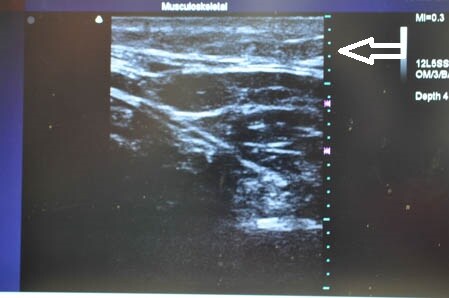

左の腰も見ておきましょう。

↓ ↓ ↓